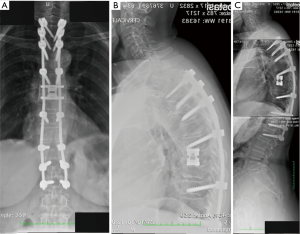

All the nine patients were in theory suitable for corpectomy and expandable titanium cage implant (7). But this approach was performed only in two of them. In fact, in 7 patients, a reconstruction of the anterior and medial spinal column was accomplished by third generation percutaneous vertebral augmentation systems (MK). In all the cases however a posterior fixation with rod and screws was always performed. The choice between one technique and the other one was made according to the signal in short tau inversion recovery (STIR) in the MRI sequences: in case of hyperintense signal to the level of the collapsed vertebra (VP), we decided for the percutaneous vertebral augmentation (Figures 3,4) (8). In absence or in case of very low STIR hyperintense signal, we chose for the standard corpectomy (Figures 5,6). Indeed, the presence of positive signal in the VP is in fact indicative of the reducibility of the vertebral soma. Moreover, in the cases of spinal canal compression the applicability of the third generation MK alone, without any posterior decompression, must not be excluded: it must be inferior to 1/3 and 2/3 respectively in case of fractures level above and below the spinal cord and any clinical signs of radicular compressions must not be identified. Otherwise, a direct posterior spinal cord decompression must be performed. Furthermore it is mandatory to evaluate the state of the anterior longitudinal ligament (ALL). In case of ossification of ALL at the level of the VP, MK has to be avoided, because a satisfactory correction of the vertebral height and a substantial management of the regional deformity might not be achieved. Mean follow-up was 18 months (range, 12–28 months). None of the patients experienced neurologic deterioration neither they showed a progression of local or regional deformity. No infections, dural tears, or spinal cord injuries occurred. No revision surgery was performed. In case of corpectomy the main blood loss and the mean surgical time were inevitably greater (9).